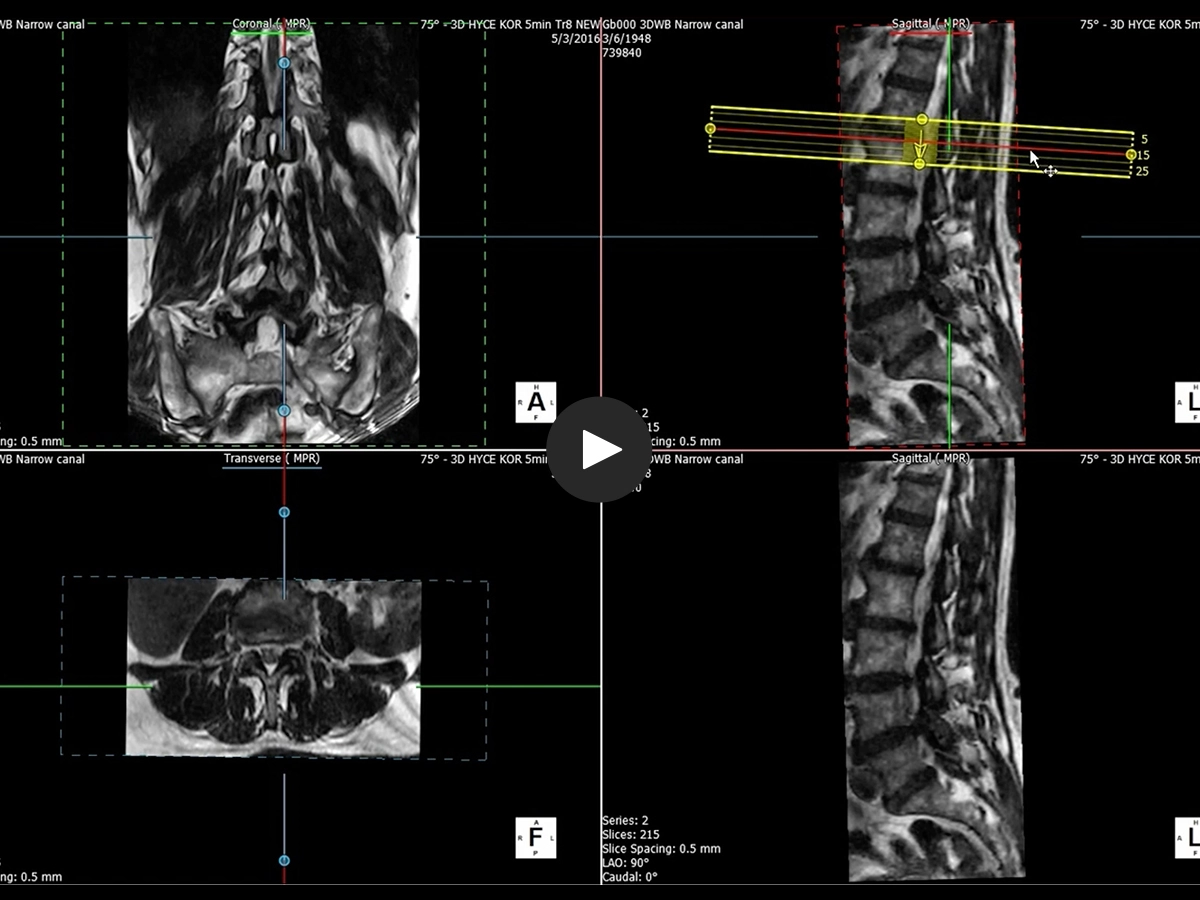

Using a 3D data MRI dataset, the 3D viewer allows the reconstruction of images in any desired direction, orthogonal and angulated as well as curved reconstructions e.g. along the spine.

• A whole 3D reconstruction allows you to interactively navigate into 3D volumes

• Flexible choice of reconstruction parameters like the number of slices and thickness.

• Real time Multi-Planar Reconstruction.

• Choose your Multi Planar reconstruction curve based on the anatomy under evaluation.